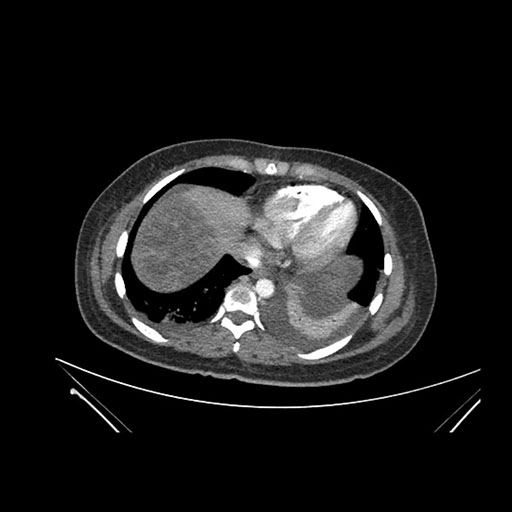

Imaging Analysis

Look through the patient's CT scan to identify any areas of concern for the necessary procedure.

Axial Arterial

Axial Venous